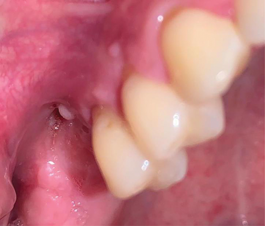

A 36-year-old male patient presented to the Oral and Maxillofacial Surgery department at NYUCD with the chief complaint of pain in the posterior right maxilla. Clinical and radiological evaluation revealed a nonrestorable maxillary second molar with a vertical root fracture and a periapical pathology (Figure 1). The patient had no significant medical history and no known drug allergies. He denied tobacco smoking and alcohol consumption, but admitted using recreational drugs, specifically five marijuana cigarettes per day and e-cigarettes. Thus, the patient was classified as American Society of Anesthesiologists (ASA) II.10

Fig 1. Preoperative CBCT scan showing a sagittal section of nonrestorable tooth No. 2 with a periapical radiolucency.

Figure 1